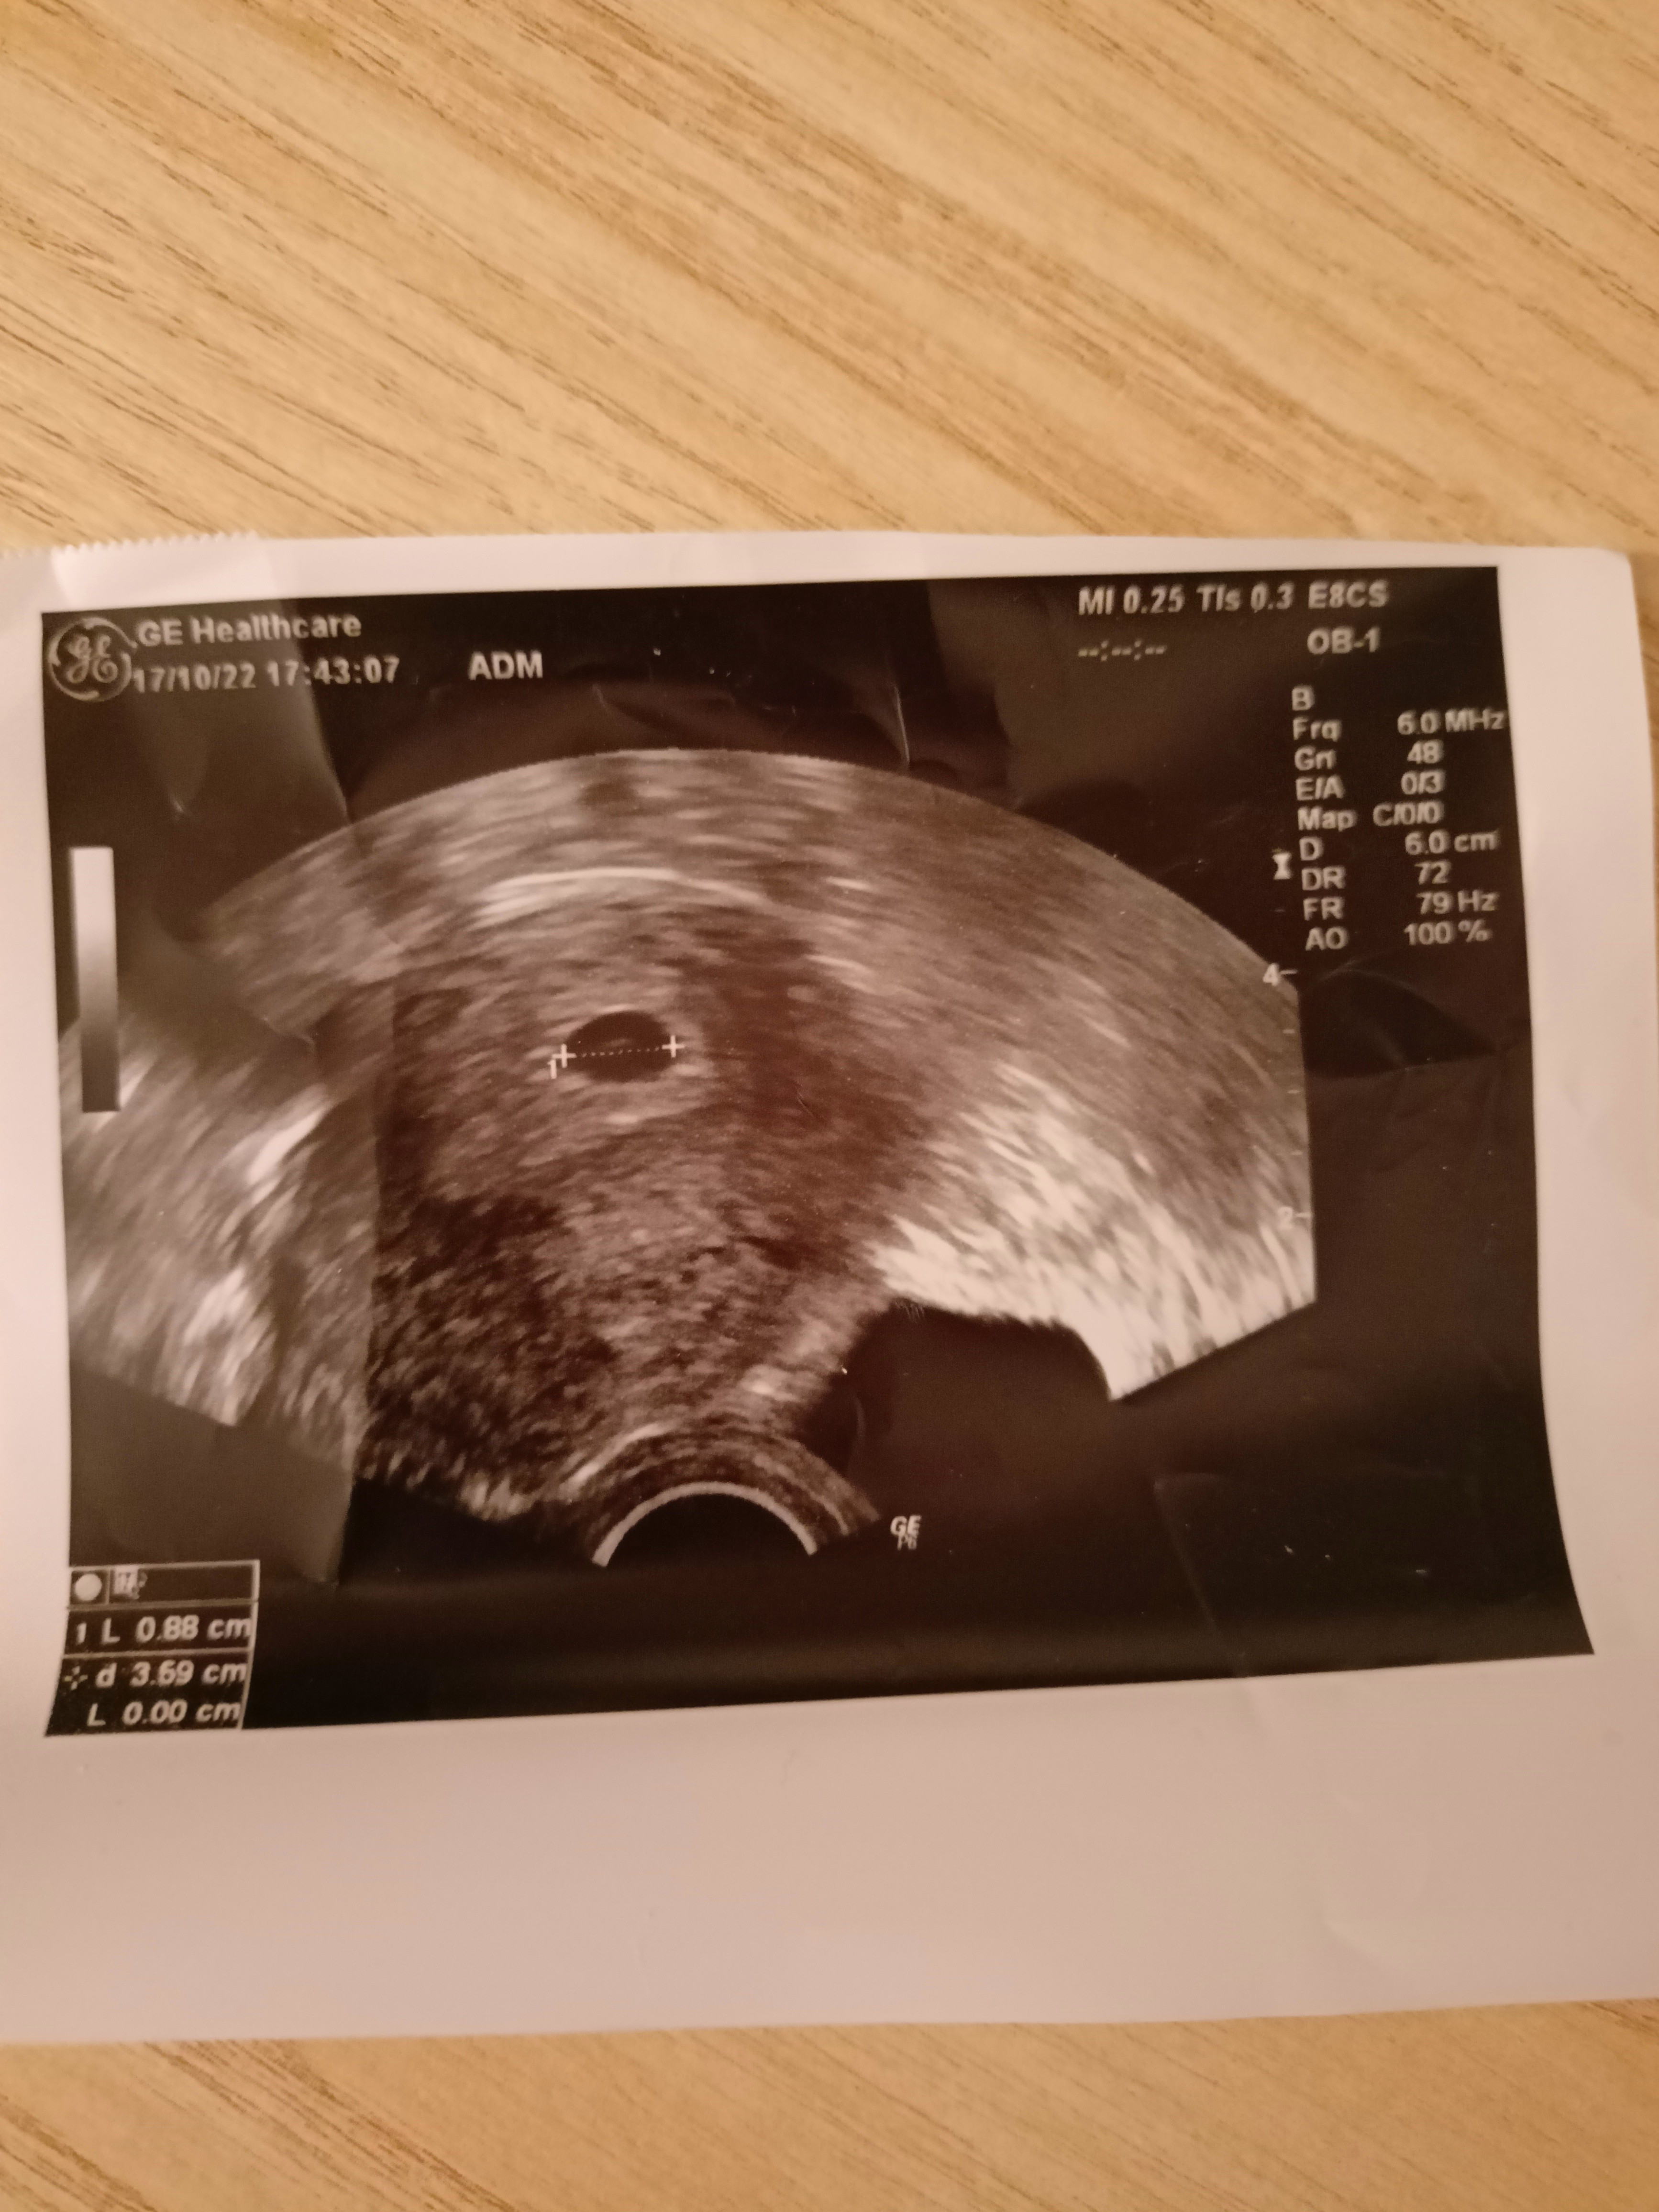

Ja po pierwszej wizycie, mam podejrzenie ciąży 2k20...

Która z Was ma jakieś doświadczenia w tym? 27 mam wizytę kolejną, wtedy się okaże. Albo pojawi się drugi zarodek, młodszy albo drugi pęcherzyk się wchłonie.![]()